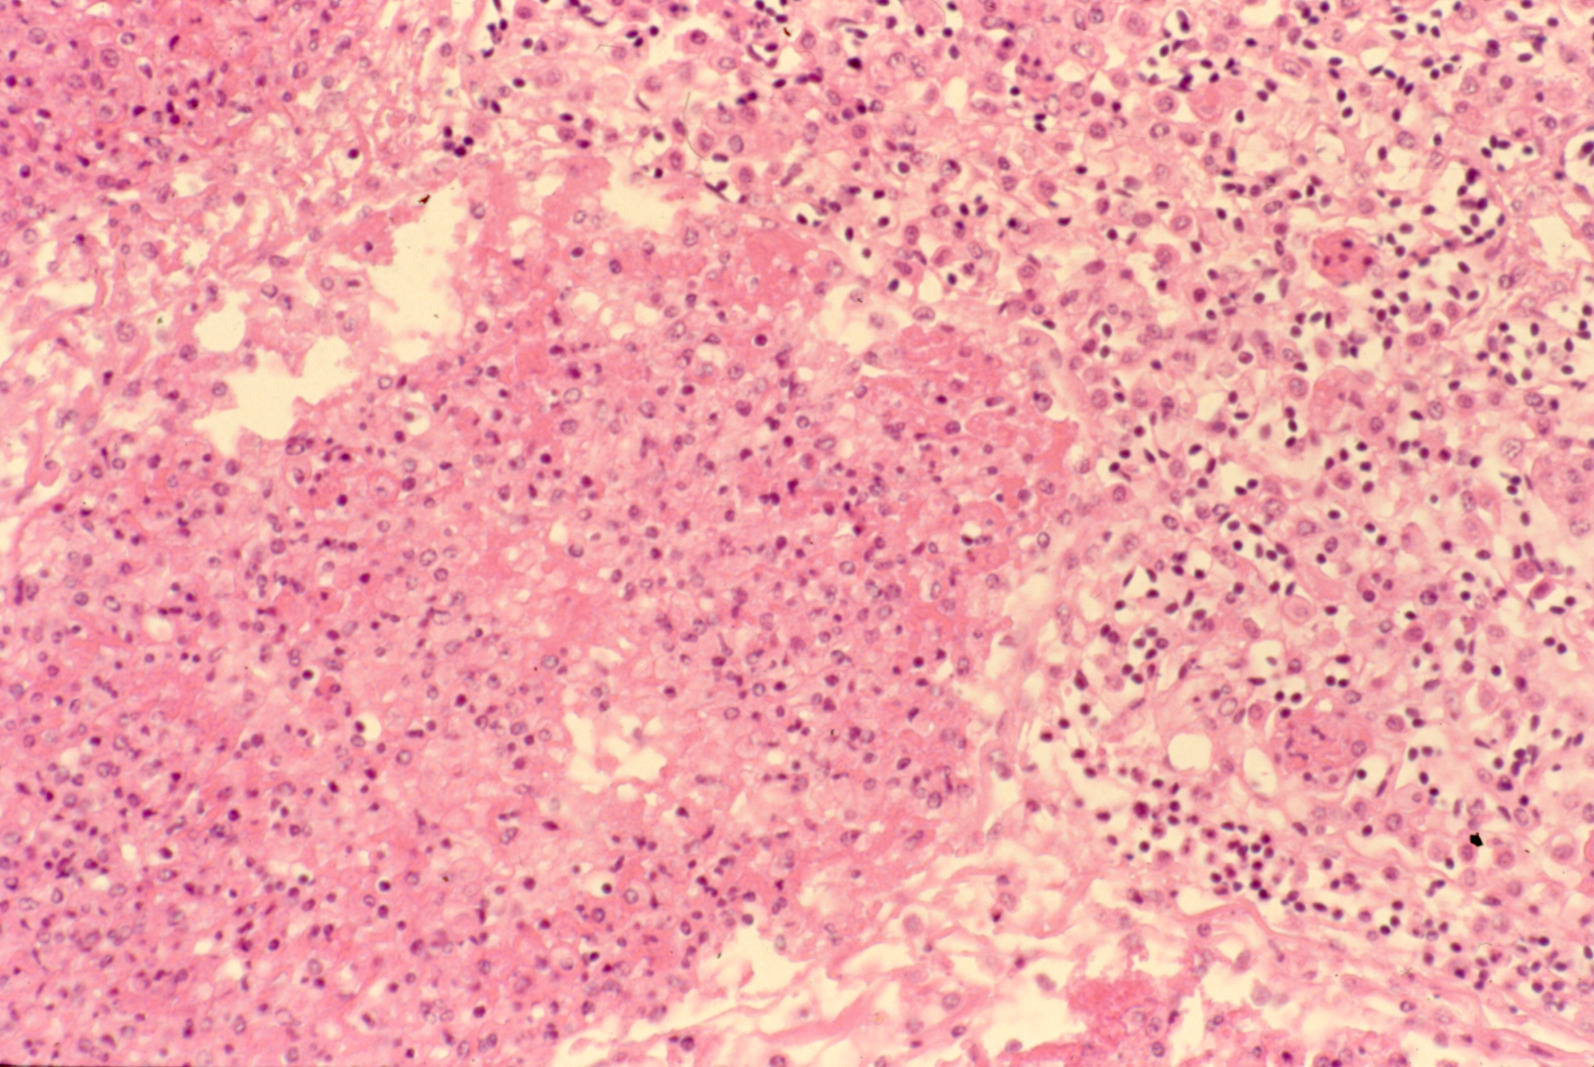

Fowl cholera (slide study set no. 19) Item Info

Fowl cholera (slide study set no. 19)

Poultry--Diseases Chicken cholera